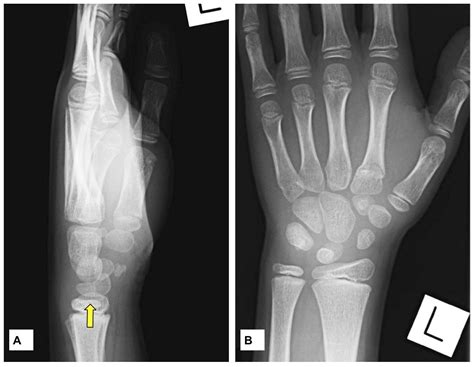

Related searches for corticated bone fragments well corticated ossific fragmentcorticated bone fragment definitionwell corticated bone fragmentcorticated ossiclewhat is a fracture fragment. These are well corticated osseous fragments that are located in characteristic places.

At times, they mimic fractures or loose bodies, proving to be a diagnostic conundrum, thus leading to misdiagnoses.

Apophysis of the 5th mt runs in a longitudinal direction; He is only seeing the endocrinologist at the end of june, should i take him to see our gp in the interim with. As the ankle is a ring structure, if one displaced fracture is seen, another should be sought. There are many different types of fracture from greenstick, hairline, and compression to oblique, impacted, and longitudinal. Joint effusions are seen with fractures and ligament and tendon injuries. Meaning of corticated medical term. The margins are well corticated and this has the appearance of an old partially united fracture. Aim • to differentiate between fracture mimics and fractures. Etymologically, the word cortex in medicine is from the latin word, literally meaning bark' of a tree. Apophysis of the 5th mt runs in a longitudinal direction; Result from a _____ force on the bone 3. A fracture is when the continuity of a bone is broken. Posterior talar process fracture with injury to the lateral tubercle caused by inversion or extreme equinus. The corticated appearance as well as the absence of overlying soft tissue swelling is consistent with a chronic ununited fracture. Can be associated with ? This site might help you. This is a fracture of the odontoid process at its os odontoideum: